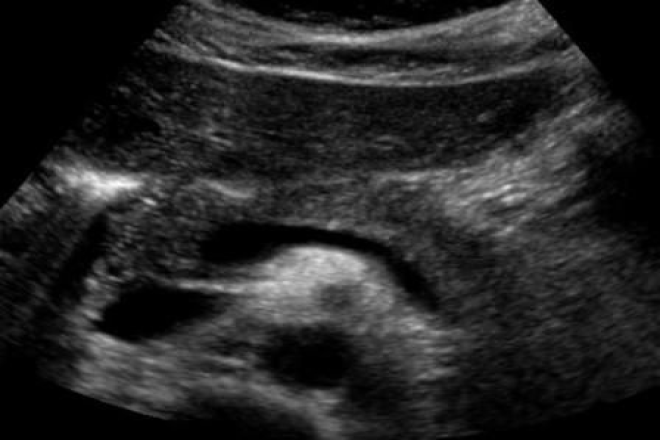

Pancreatitis crónica: en estadios avanzados es fácil su reconocimiento, por presencia de calcificaciones intra ductales, dilatación del conducto pancreático principal, lesiones quísticas o sólidas cercanas al conducto pancreático, atrofia glandular, y parénquima heterogéneo. En el grado moderado la ecogenicidad es homogénea por fibrosis hiperecogénica. Así como infiltración grasa.